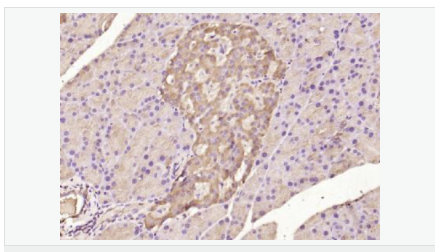

| 產(chǎn)品應(yīng)用 | WB=1:500-2000 ELISA=1:5000-10000 IHC-P=1:100-500 IHC-F=1:100-500 Flow-Cyt=1μg /test IF=1:100-500 (石蠟切片需做抗原修復(fù)) not yet tested in other applications. optimal dilutions/concentrations should be determined by the end user. |

| 細(xì)胞定位 | 細(xì)胞核 細(xì)胞漿 |

| 產(chǎn)品介紹 | ATF6 is a transcription factor that acts during endoplasmic reticulum stress by activating unfolded protein response target genes. It binds DNA on the 5'-CCAC[GA]-3'half of the ER stress response element (ERSE) (5'-CCAAT-N(9)-CCAC[GA]-3') and of ERSE II (5'-ATTGG-N-CCACG-3'). Binding to ERSE requires binding of NF-Y to ERSE. ATF6 could also be involved in activation of transcription by the serum response factor. ATF6 exists as a homodimer and heterodimer with ATF6 beta. The dimer interacts with the nuclear transcription factor Y (NF-Y) trimer through direct binding to NF-Y subunit C (NF-YC). It also interacts with the transcription factors GTF2I, YY1 and SRF. Under ER stress the cleaved N-terminal cytoplasmic domain translocates into the nucleus. The basic domain of ATF6 functions as a nuclear localization signal and the basic leucine zipper domain is sufficient for association with the NF-Y trimer and binding to ERSE. During the unfolded protein response an approximately 50 kDa fragment containing the cytoplasmic transcription factor domain is released by proteolysis. The cleavage seems to be performed sequentially by site 1 and site 2 proteases. ATF6 is N glycosylated, phosphorylated in vitro by MAPK14/P38MAPK and belongs to the bZIP family. Function: Transcription factor that acts during endoplasmic reticulum stress by activating unfolded protein response target genes. Binds DNA on the 5'-CCAC[GA]-3'half of the ER stress response element (ERSE) (5'-CCAAT-N(9)-CCAC[GA]-3') and of ERSE II (5'-ATTGG-N-CCACG-3'). Binding to ERSE requires binding of NF-Y to ERSE. Could also be involved in activation of transcription by the serum response factor. Subunit: Homodimer and heterodimer with ATF6-beta. The dimer interacts with the nuclear transcription factor Y (NF-Y) trimer through direct binding to NF-Y subunit C (NF-YC). Interacts also with the transcription factors GTF2I, YY1 and SRF. Subcellular Location: Endoplasmic reticulum membrane; Single-pass type II membrane protein. Processed cyclic AMP-dependent transcription factor ATF-6 alpha: Nucleus. Note=Under ER stress the cleaved N-terminal cytoplasmic domain translocates into the nucleus. Tissue Specificity: Ubiquitous. Post-translational modifications: During unfolded protein response an approximative 50 kDa fragment containing the cytoplasmic transcription factor domain is released by proteolysis. The cleavage seems to be performed sequentially by site-1 and site-2 proteases. N-glycosylated. The glycosylation status may serve as a sensor for ER homeostasis, resulting in ATF6 activation to trigger the unfolded protein response (UPR). Phosphorylated in vitro by MAPK14/P38MAPK. Similarity: Belongs to the bZIP family. ATF subfamily. Contains 1 bZIP (basic-leucine zipper) domain. SWISS: P18850 Gene ID: 22926 Database links: Entrez Gene: 22926 Human Entrez Gene: 226641 Mouse Omim: 605537 Human SwissProt: P18850 Human Unigene: 492740 Human Important Note: This product as supplied is intended for research use only, not for use in human, therapeutic or diagnostic applications. |